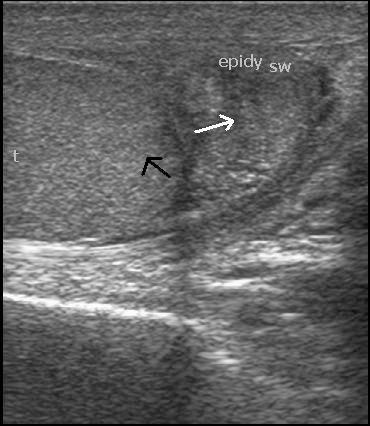

腺瘤样瘤是男性睾丸旁区域的一种良性间皮肿瘤,但也可发生于女性生殖道。附睾是最常受累的部位,占睾丸旁肿瘤的32%。我们通过细胞病理学诊断了一例24岁男性的腺瘤样瘤,该患者自2个月前起右侧附睾出现肿块。结节手术切除后,通过组织病理学和免疫组织化学确诊。细针穿刺抽吸活检(FNAC)是一种快速、可靠且经济高效的诊断工具,用于术前诊断以做出适当的手术决策。病理学家应了解此类病变的细胞学特征,以便将其与其他睾丸旁病变区分开来。

https://cdn.ncbi.nlm.nih.gov/pmc/blobs/83ff/3649525/ff9e9db66b47/jscr-2012-4-11fig3.jpg

https://cdn.ncbi.nlm.nih.gov/pmc/blobs/83ff/3649525/2334f746716e/jscr-2012-4-11fig1.jpg

https://cdn.ncbi.nlm.nih.gov/pmc/blobs/83ff/3649525/6e4283fe47ec/jscr-2012-4-11fig2.jpg